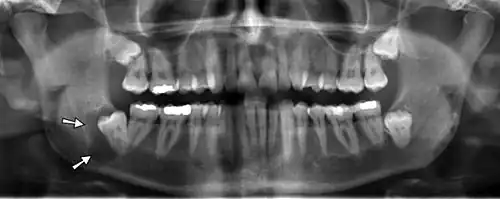

On an x-ray, cysts appear as radiolucent (dark) areas with radiopaque (white) borders.[7] However, cysts in maxillary sinus, also known as antrum, can appear radiopaque as the surrounding air absorbs fewer photons than the cystic fluid content.

Cysts are usually unilocular, but may also be multilocular. Sometimes aspiration (fine needle aspiration) is used to aid diagnosis of a cystic lesion; e.g., fluid aspirated from a radicular cyst may appear straw-colored and display shimmering due to cholesterol content.[5] Almost always, the cyst lining is sent to a pathologist for histopathologic examination after it has been surgically removed. This means that the exact diagnosis of the type of cyst is often made in retrospect, and definitive treatment can be made for the patient.